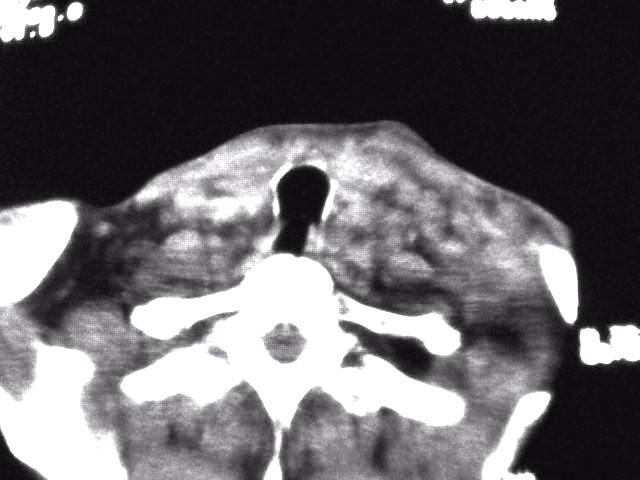

颈部层厚10mm间距10mm连续扫描及增强扫描共24层示:左侧下颈部胸锁乳突肌内侧区域内可见多发软组织结节,密度不均,内可见斑片状低密度区,大小不等,部分融合成块,左侧融合成一块者大约9.0x5.4,与周围肌肉、血管等结构界面不清,骨质未见明显浸润影。左侧锁骨下可见多个软组织结节,与周围界限尚清,左侧锁骨上窝内可见一大软组织肿物,大小约4.7x3.7cm,内密度欠均匀中心可见低密度区。

考虑:左侧颈部及双侧锁骨下多发淋巴结肿。非何杰金氏淋巴瘤可能性大,建议进一步检查。